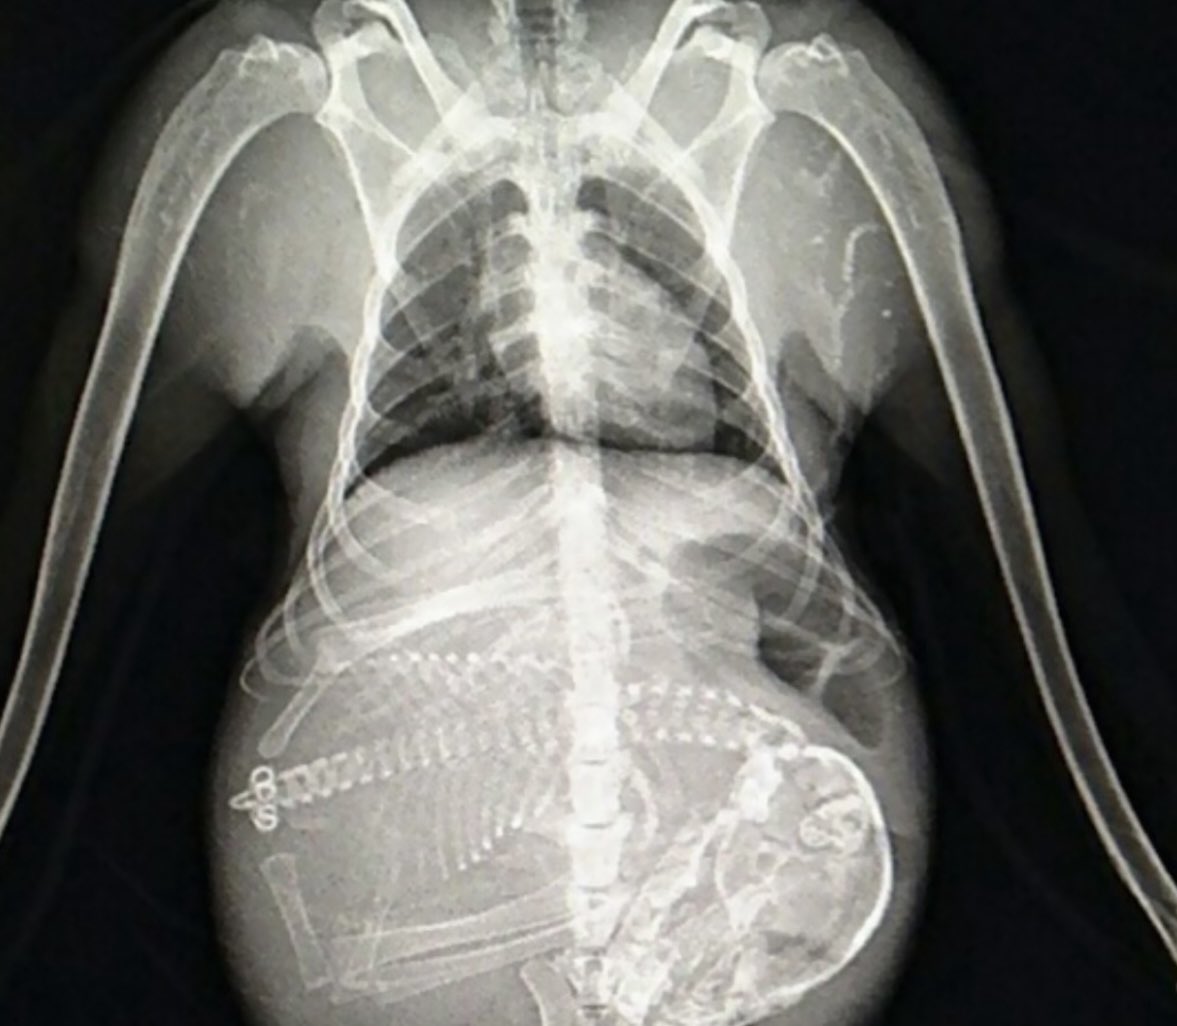

It isn't a rare case - it is a common one. In our practice, we work hard to mitigate every possible risk factor that might prevent need for fusion of an unstable head-neck junction or upper spine. And sometimes we reach the end of that road. Sometimes we meet the patient late...

Thank you for all the support and care. Here’s her story once more, just in case. Sure hope the #HealthInsurance #CEOs ar #cigna #BCBS #UHC and others are reading. #CCI #POTS And again, @RepKimSchrier @PattyMurray @SenatorCantwell Wanna make a law?? huffpost.com/entry/brain-su…